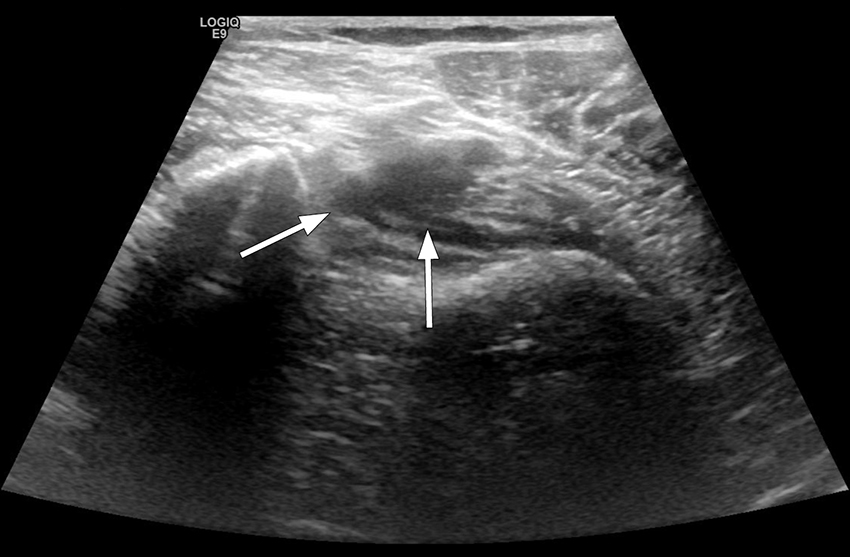

The next day, she still had severe pain in her popliteal fossa and upper leg, and asked a colleague in the Department of Radiology to carry out an ultrasound examination to rule out deep vein thrombosis. Thrombus was then revealed in the distal popliteal vein (Figure 1).

Figure 1 Ultrasound image of right lower extremity, patient examined with legs hanging over the edge of the bed. Distal…

Figure 1 Ultrasound image of right lower extremity, patient examined with legs hanging over the edge of the bed. Distal popliteal vein shown upon compression. A sickle-shaped shadow is seen in the centre of the image, and the vein cannot be compressed, as is the case for intraluminal content.